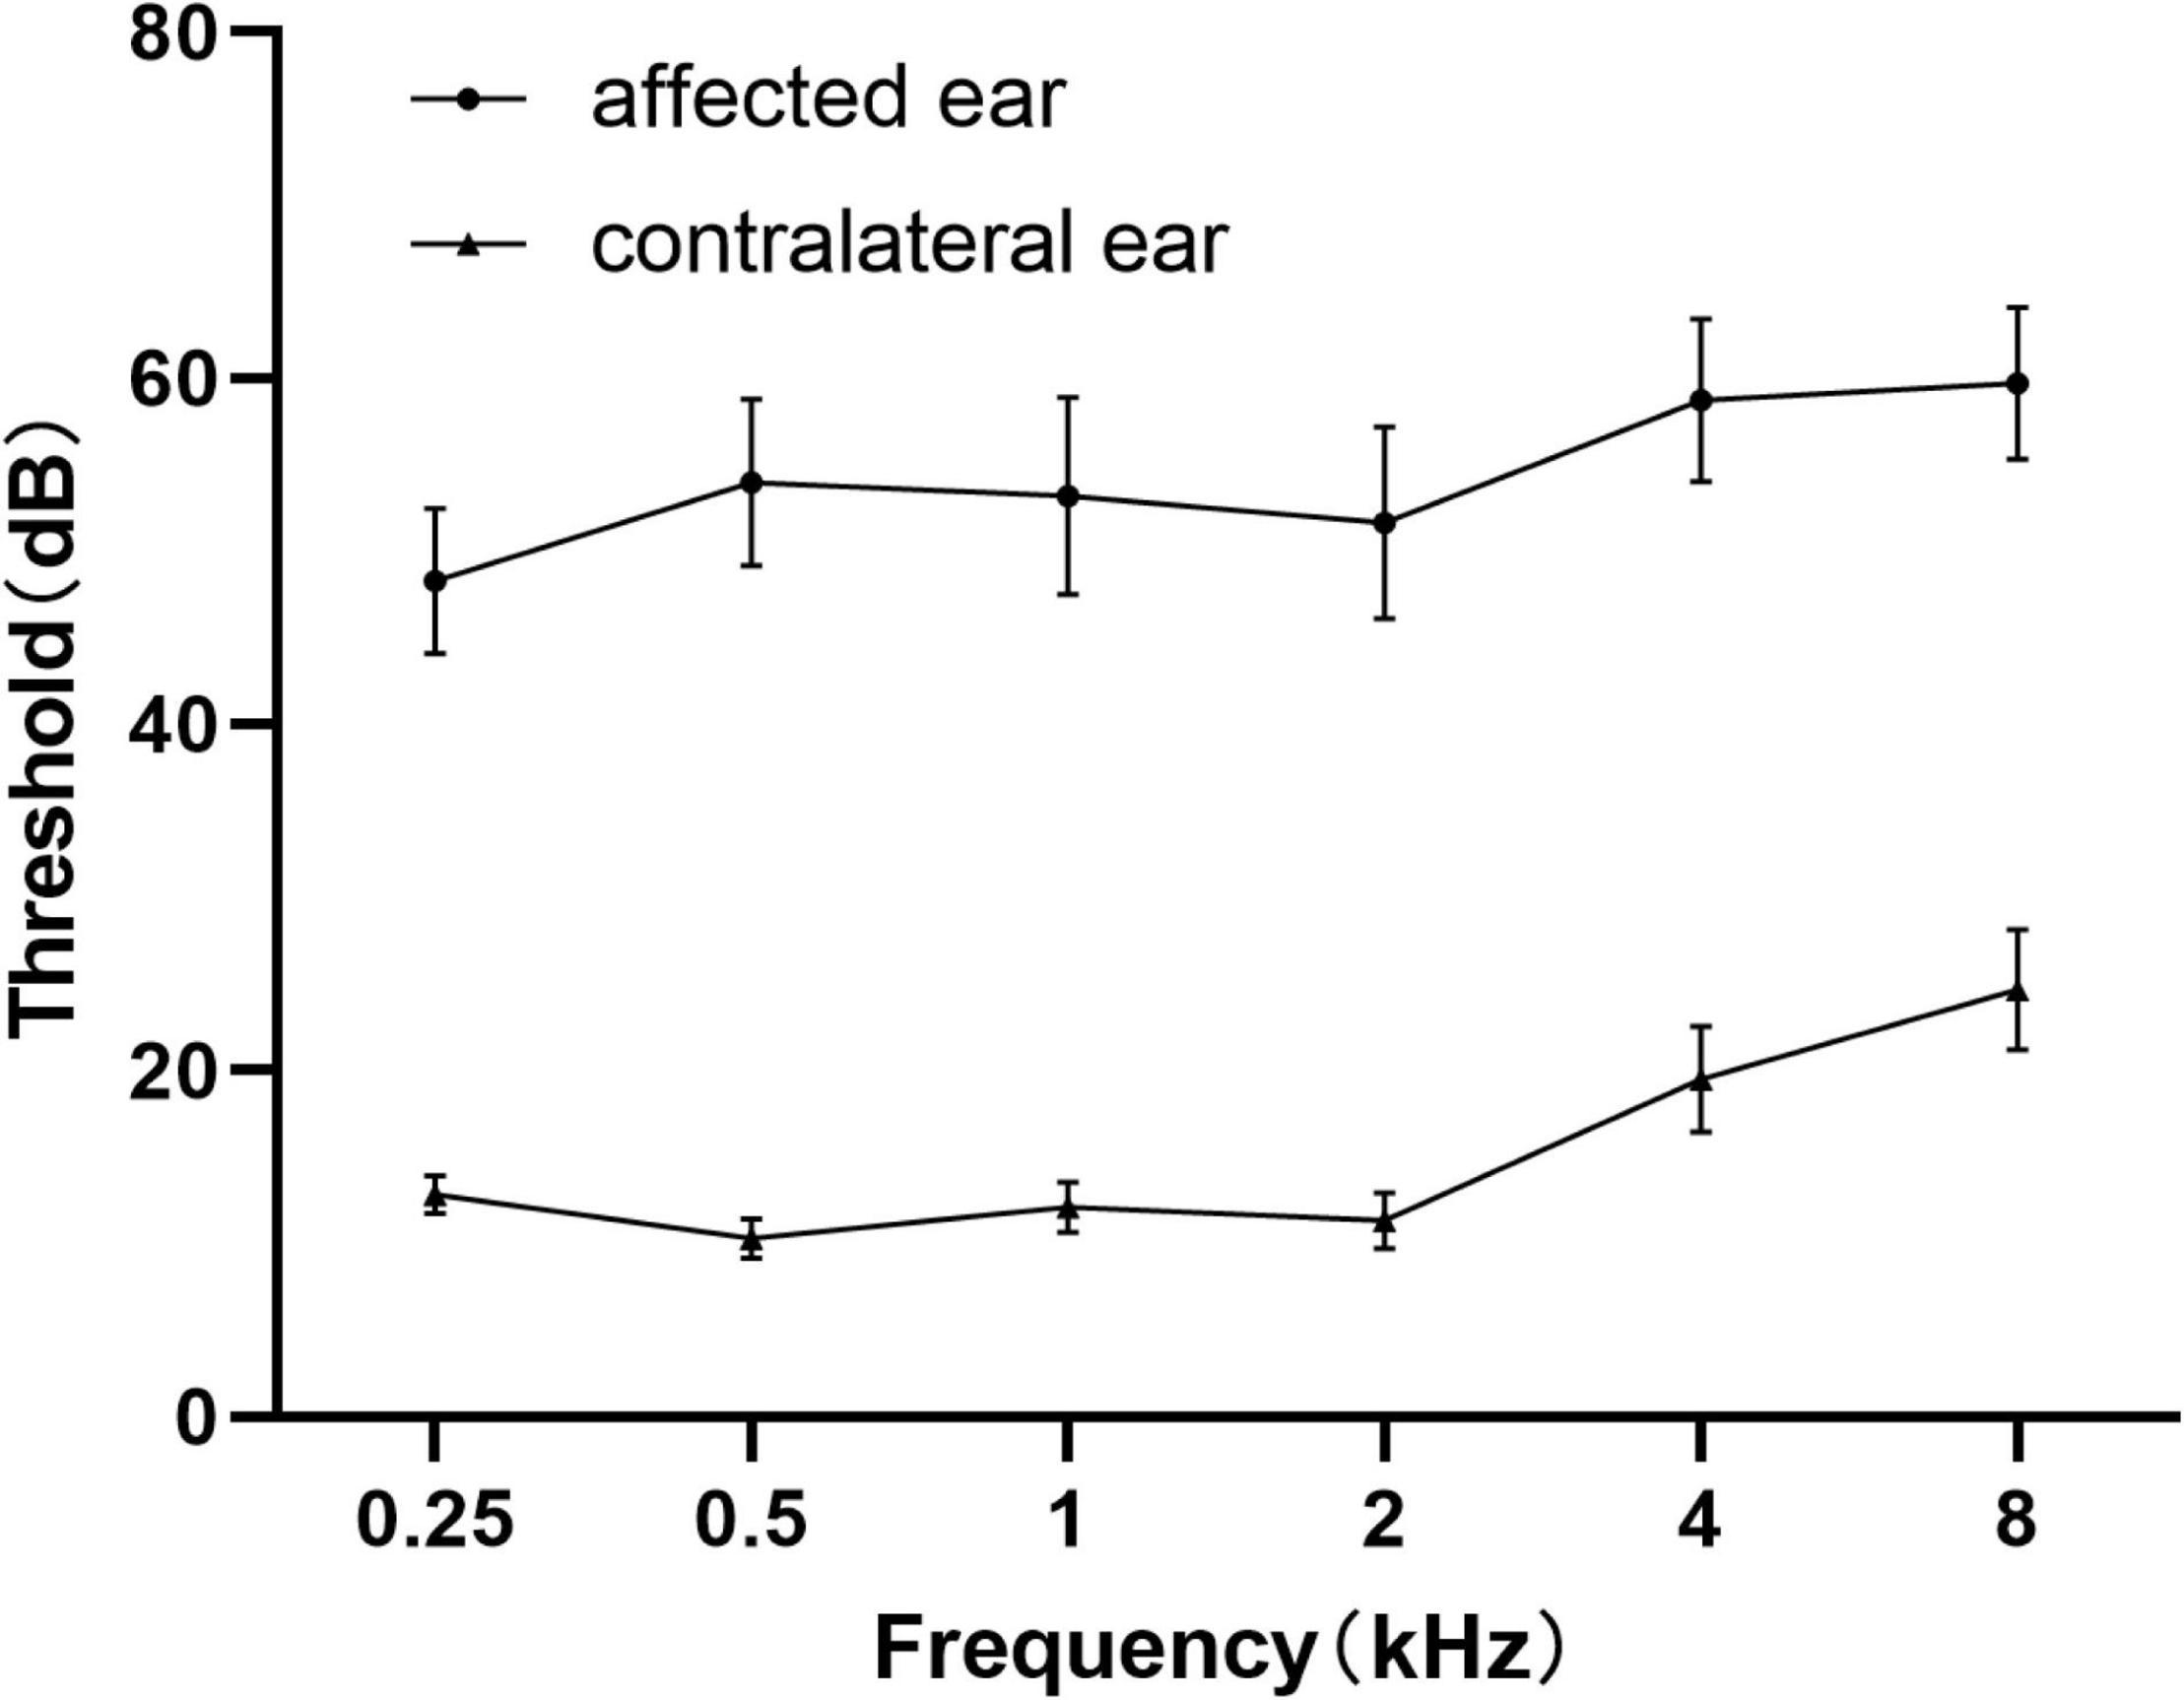

Demographics and clinical characteristic data of all the unilateral SSNHL patients and healthy controls were summarized in Table 1 and Figure 3. No significant differences were found in terms of age, gender, education level.

Figure 3. Average pure tone audiograms for patients with SSNHL averaged over both ears at different frequencies. Data are presented as mean ± SEM. SEM, standard error of mean.